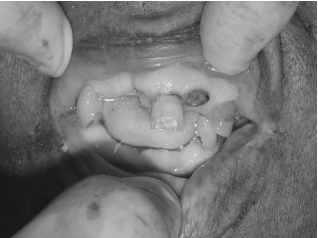

Considerando a figura acima, obtida em uma necropsia de um cadáver não identificado, assinale a opção correta.